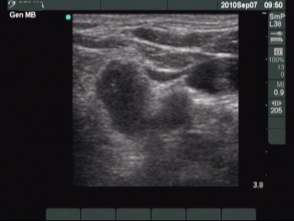

Second session (second row of images):

Clinical presentation: the patient became aware of mild neck discomfort lasting for 2 days.

I removed 3.5 ml serous-watery fluid and administered 1.5 mL ethanol.